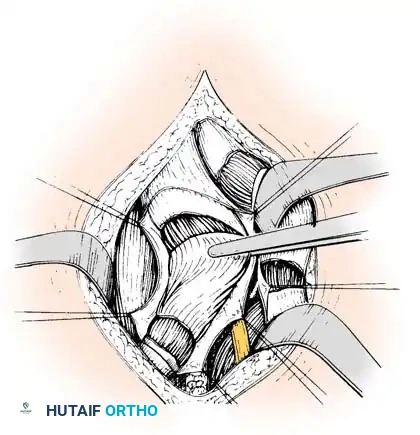

* Identify the hamstrings via blunt dissection. Isolate the semimembranosus muscle and incise its tendon sheath longitudinally.

* Divide the tendinous fibers of the semimembranosus on its deep (anterior) surface transversely at two distinct levels, leaving the underlying muscle fibers completely intact.

Forceps everting semimembranosus muscle to expose tendinous portion; division at two levels.

- Next, expose the semitendinosus tendon. Divide the distal portion of the tendon obliquely up to its muscle fibers. Depending on the severity of the contracture, incise the tendon transversely or perform a formal Z-plasty.

- Extend the knee and flex the hip simultaneously. The sectioned tendinous portion of the semimembranosus will slide smoothly over the intact muscle belly, achieving the desired lengthening.